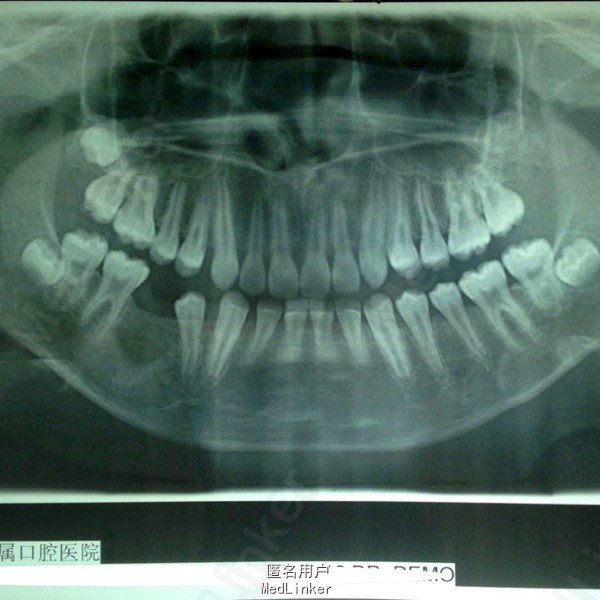

偶然发现右下颌骨包块2月 患者男,11岁,2月前发现右下颌骨区包块,于当地医院就诊,未明确诊断,建议上级医院就诊,遂入我院。

颌面部不对称,口内见右侧下颌颊侧膨隆,大小约3cm*4cm,质硬,不活动,无压痛。黏膜正常。85龋坏,滞留。44-46根尖低密度影,周围高密度致密影,45埋伏阻生。

右下颌骨含牙囊肿 局部开窗引流术,拔除滞留乳牙及埋伏阻生牙。同期取少量标本病检。

术后病检提示含牙囊肿。随访提示局部病变区囊肿缩小,新骨形成。目前仍处于随访阶段,并拟安排后续正畸治疗。 讨论:颌骨囊肿治疗方式非常多,传统填塞碘仿纱条,植骨(粉),引流~考虑患者年龄,后续治疗不适合做种植手术,植骨对正畸治疗有一定影响。综合考虑选择引流法,也取得了预期效果。但囊肿有向成釉细胞瘤转化可能,需术前告知患方,并坚持随访。